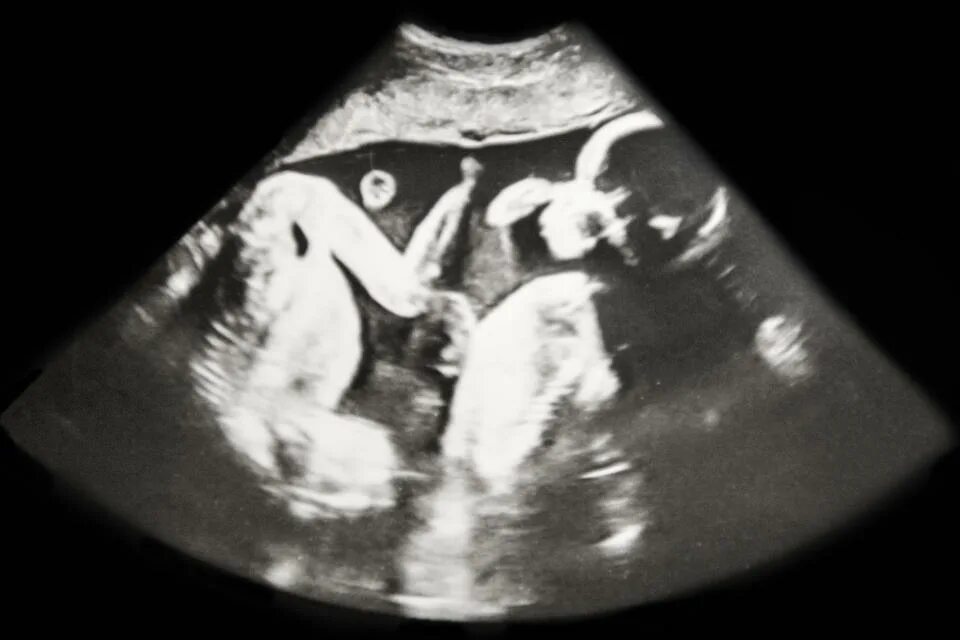

27 недель беременности двойня